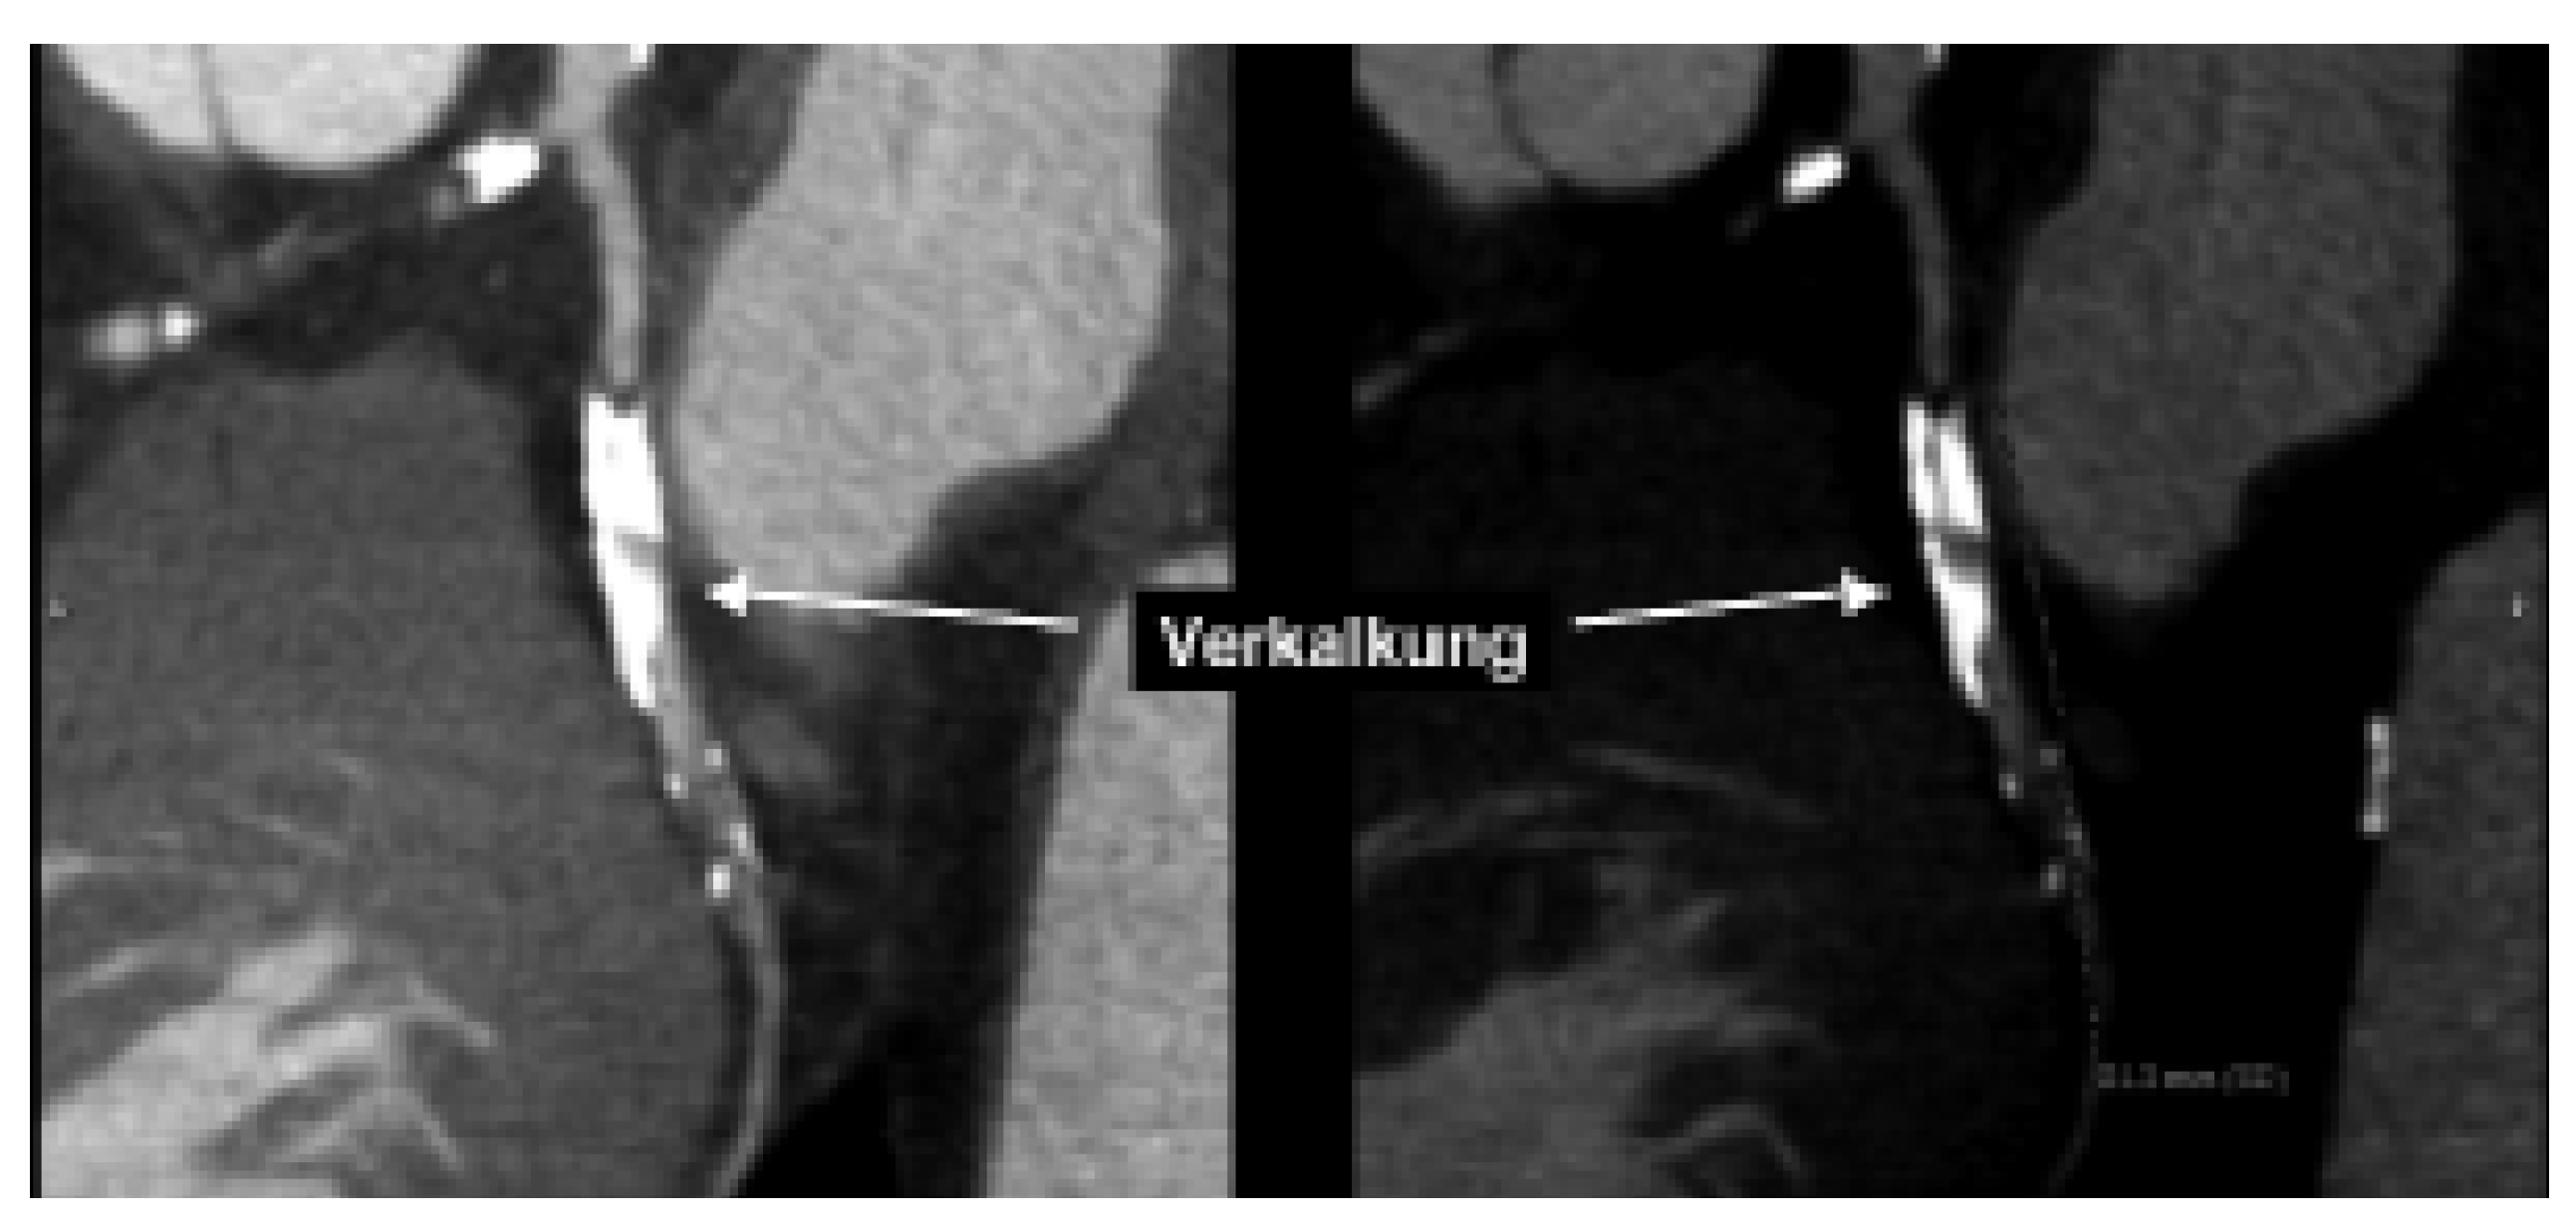

Abbildung 3. Stents stellen ebenfalls eine Herausforderung dar. Zwar können Stents sehr gut v.a. dreidimensional dargestellt werden (links), doch die Beurteilung des Lumens ist häufig beeinträchtigt.

Verkalkungen der Herzkranzgefässe beeinträchtigen allerdings auch erheblich die Darstellung des Lumens in der computertomographischen Angiographie (Abb. 2). Somit lässt sich in stark verkalkten Gefässen meist nicht sagen, ob es sich nur um ein krankes, d.h. arteriosklerotisch verändertes Koronarsegment handelt, oder ob es auch hämodynamisch relevant eingeengt ist. Vor allem bei älteren PatientInnen und solchen mit Diabetes und/oder Niereninsuffizienz, welche ausgeprägte Verkalkungen aufweisen, ist daher keine schlüssige Beurteilung des Lumens möglich. Zudem kann die EKG-getriggerte Untersuchung bei hoher Herzfrequenz, bei Vorhofflimmern und anderen Rhythmusstörungen, die bei etwa 5% der Patienten zu finden sind, nicht durchgeführt werden. Schliesslich sollte bei Patienten mit schwerer Herzinsuffizienz die Volumenbelastung durch das Kontrastmittel in Betracht gezogen werden. Auch durch Stents verursachte Artefakte stellen ein diagnostisches Problem dar (Abb. 3). Obschon die neuesten CT-Geräte sehr genau die Stent-Länge und den Durchmesser erfassen können, ist eine sichere Beurteilung des Lumens in vielen Fällen noch nicht möglich. Da bei der koronaren Herzkrankheit die Frage nach einer Intervention im Vordergrund steht, sei es eine kathetertechnische Stent-Implantation oder eine Bypass-Operation, ist die Erfassung von Koronarstenosen das Hauptziel dieser Untersuchungen. Entsprechend ist diese Einschränkung der Aussagekraft der computertomograpischen Koronarangiographie durch Gefässwandverkalkungen ein grosser Nachteil dieser Methode. Zusammenfassend ist daher der negativ prädiktive Wert der computertomographischen Koronarangiographie sehr hoch, d.h. bei fehlendem Nachweis von Kalzium und Einengungen lässt sich mit an Sicherheit grenzender Wahrscheinlichkeit eine koronare Herzkrankheit ausschliessen. Der positive prädiktive Wert behandlungsbedürftiger Koronarstenosen ist aber vor allem in der älteren Population, in welcher die koronare Herzkrankheit besonders häufig ist, immer noch stark eingeschränkt (Abb. 4). Unseres Erachtens können momentan wichtige klinische Entscheidungen (wie z.B., ob ein Patient aufgrund des Koronarbefundes mittels ACBPOperation oder PCI behandeln werden muss) nicht ausschliesslich anhand des CT-Befundes gefällt werden. Das Vorhandensein von Gefässverkalkungen hat den Einsatz dieser vielversprechenden Technik auch in anderen Gefässabschnitten (wie in den Karotiden [8,9]) beschränkt.